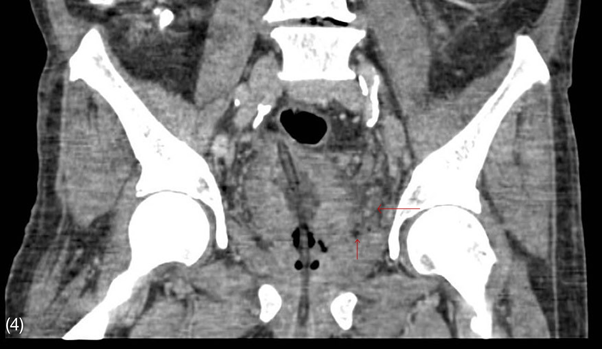

Figure 4 Contrast-enhanced CT scan of the abdomen in coronal view.

Thickened bladder walls with presence of emphysema and fluid in the prevesical space.